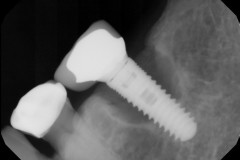

This young patient was self-conscious about the appearance of her short teeth and gummy smile. Through crown lengthening and tooth whitening procedures, we were able to create a beautiful, more mature smile.